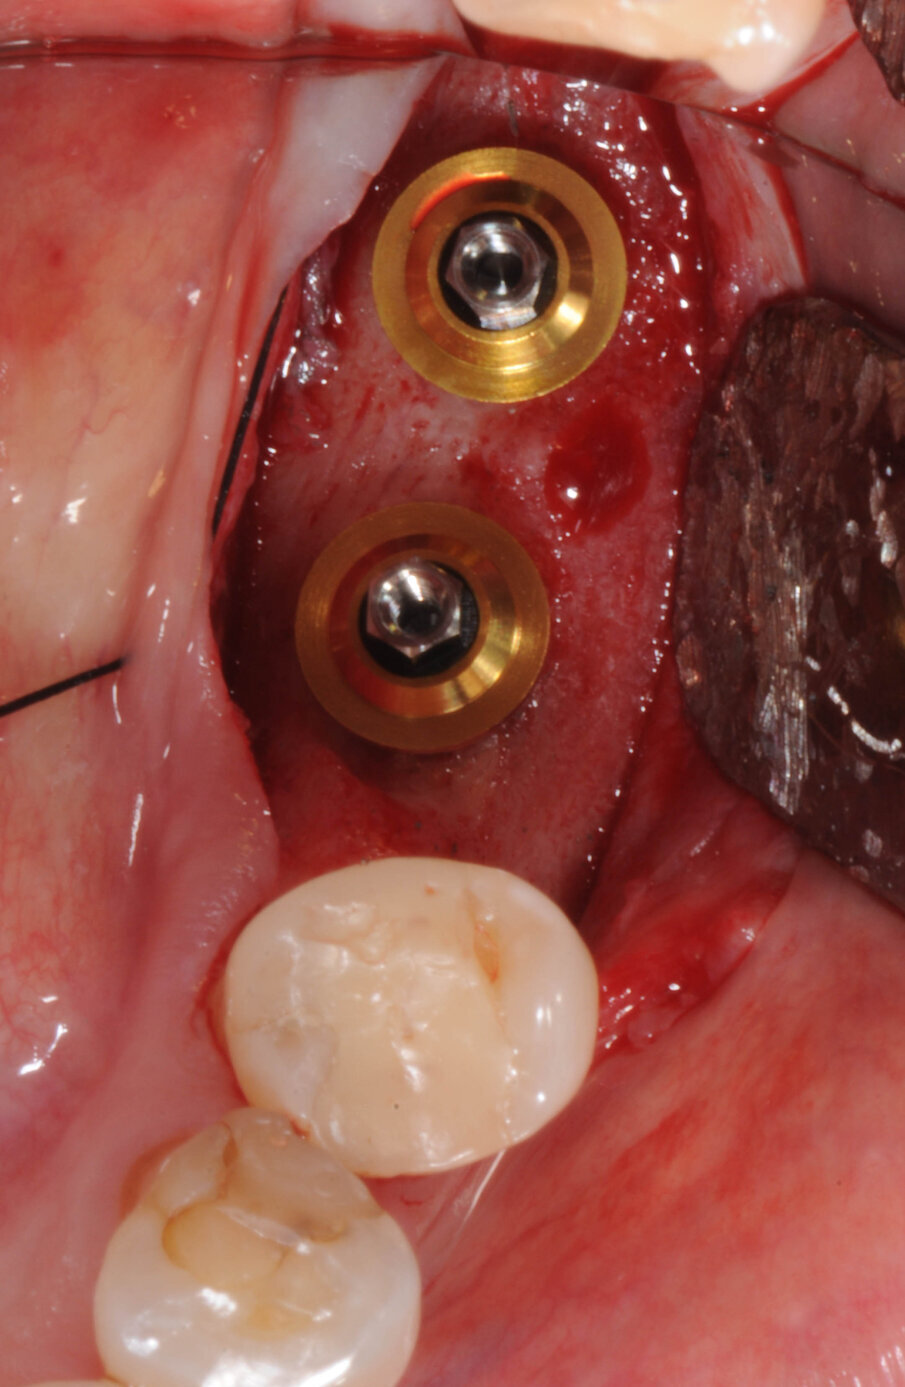

Il giorno della chirurgia fu somministrata una terapia antibiotica profilattica, per mezzo di amoxicillina più acido clavulanico, della durata di sei giorni. Dopo somministrazione di anestesia locale con Articaina al 2% 1:100000, fu eseguita un’incisione crestale estesa nel solco del dente 35 senza incisioni di rilascio. Furono eseguite le osteotomie a bassi numeri di giri senza irrigazione come da protocollo BTI e furono inseriti due impianti BTI CORE 4,5X3,75. Al di sopra degli impianti fu collocato osso di recupero dalla fresatura mischiato con PRGF e il tutto fu protetto da due membrane di fibrina ottenute per centrifugazione del sangue della paziente con tecnica Endoret PRGF. Furono applicate suture a punti staccati con filo Supramid Braun 5.0 (Figg. 5-7).